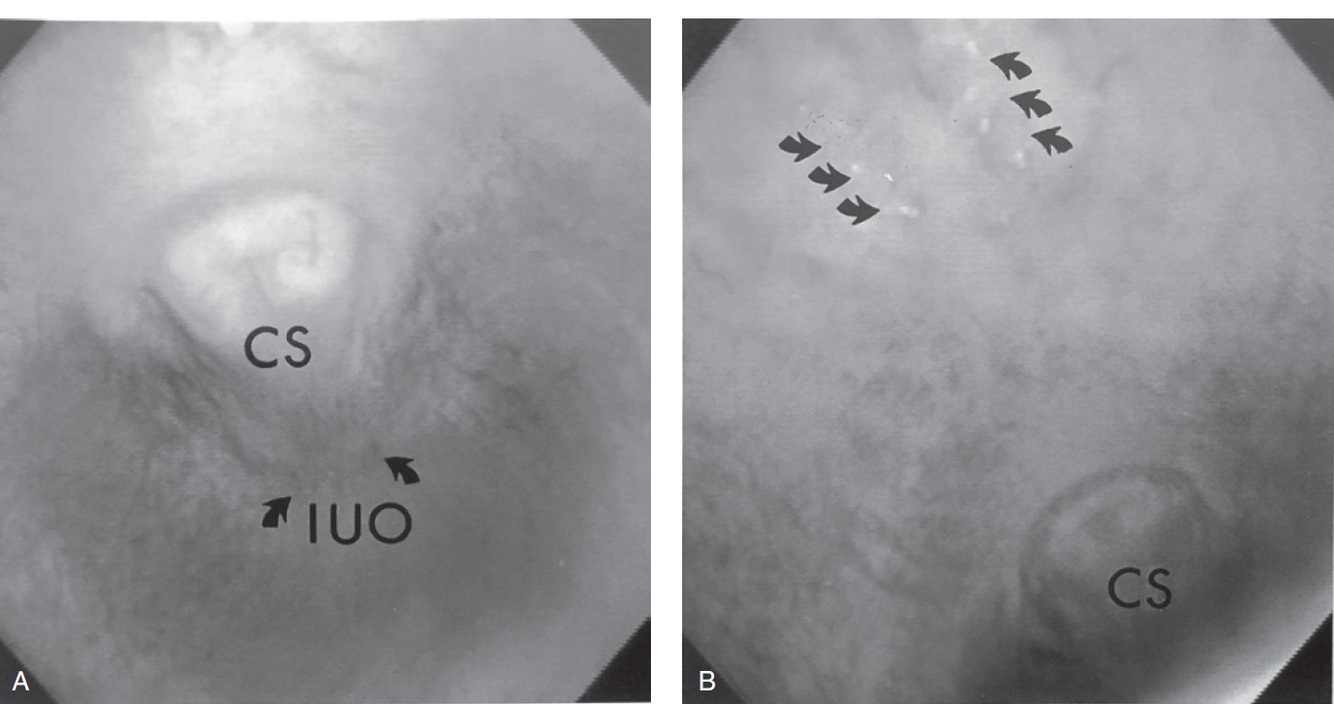

Figure 67-3. Endoscopic images of the urethra revealing distention at the level of the ischial arch (A) and a urethral stricture at the site of a previous obstructing urethrolith (B). Both images were recorded approximately 1 year following the initial examination.

Figure 67-7. Four endoscopic images showing the variable appearance of urethral rents (arrows) causing hematuria at the end of urination in geldings or hemospermia in stallions. A consistent finding is that urethral rents are located along the concave (or caudal) aspect of the urethra at the level of the ischial arch.